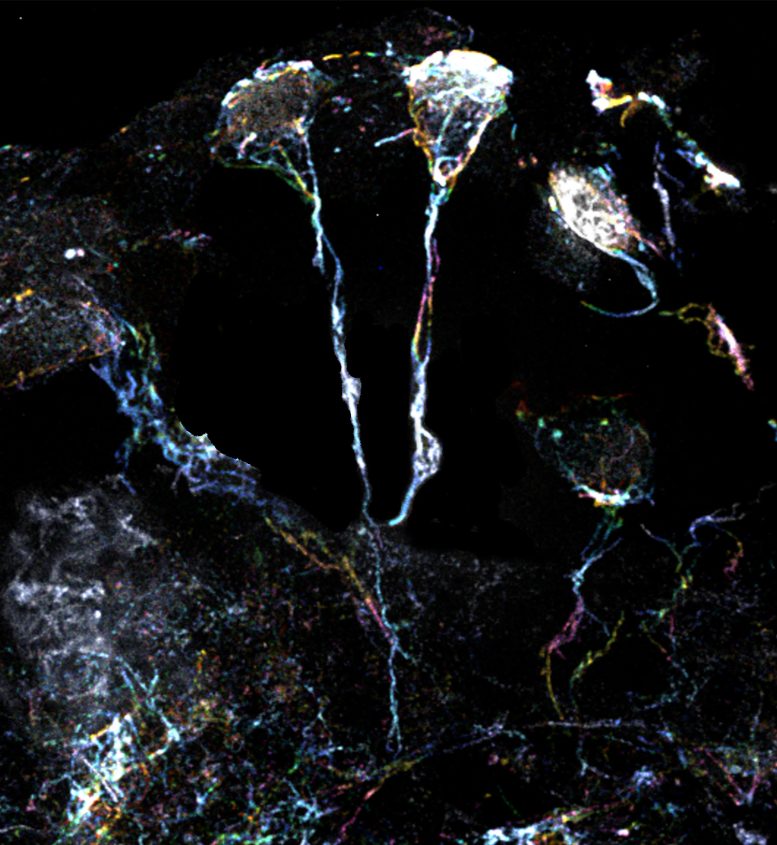

科學(xué)家團(tuán)隊(duì)使用放大倍數(shù)為10倍的超分辨率顯微鏡檢查了果蠅休眠神經(jīng)干細(xì)胞的標(biāo)志性微小纖維結(jié)構(gòu)。這些細(xì)微結(jié)構(gòu)的直徑約為1.5μm(比人類(lèi)頭發(fā)的直徑小20倍),是從細(xì)胞體延伸出來(lái)的突起,富含肌動(dòng)蛋白或蛋白質(zhì)細(xì)絲。一種特定類(lèi)型的Formin蛋白可以激活這些細(xì)絲并使其組裝。

果蠅大腦中處于休眠狀態(tài)的神經(jīng)干細(xì)胞具有富含肌動(dòng)蛋白絲的突起

果蠅大腦中處于休眠狀態(tài)的神經(jīng)干細(xì)胞具有富含肌動(dòng)蛋白絲的突起。圖片來(lái)源:杜克-新加坡國(guó)立大學(xué)醫(yī)學(xué)院